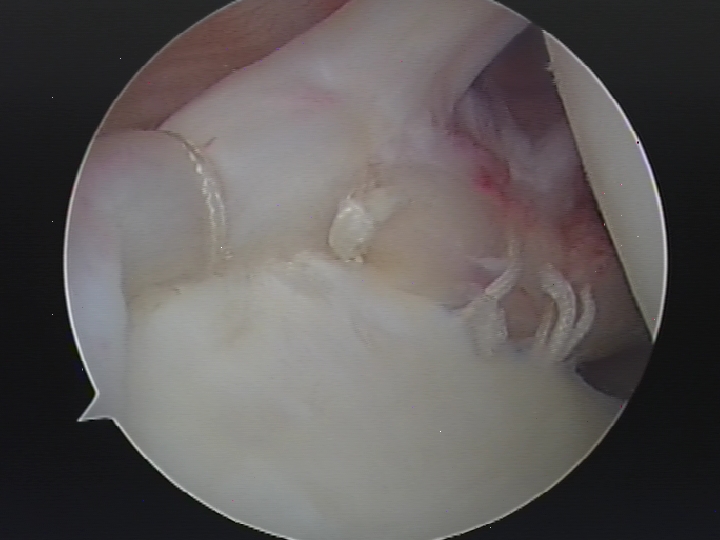

- Arthroscopic (key hole) surgery is the surgical treatment of choice in patients with symptomatic SLAP injuries. About 2-3 incisions of ½ cm to 1 cm are needed and a telescope is passed into the shoulder through one of these incisions. Special surgical instruments are passed through the other incisions. The injury is initially assessed and graded. There are 4 grades described and further treatment of the injury depends on the grade of injury. The advantage of keyhole surgery is that it is less traumatic and so recovery is quicker. It is usually carried out as a day procedure. Loss of movement of the shoulder is rare after arthroscopic repair. Debridement of the SLAP tear: If the tear is a small and at the edge of the labrum, the loose portion of the labrum is trimmed to a smooth edge. Arthroscopic repair of the SLAP tear: With this surgery, the upper part of the labrum is repaired and reattached to the bone by using special suture anchors. This type of surgery is practiced for tears that are unstable. Arthroscopic tenodesis of the biceps tendon: With this surgery, the tendon attached to the upper part of the labrum is cut and reattached to the upper humerus. The principle behind this surgery is that the tendon will not pull on the torn labrum and the symptoms will improve. This surgery is practiced in degenerative, unstable SLAP injuries.

Arthroscopic repair of SLAP tear.